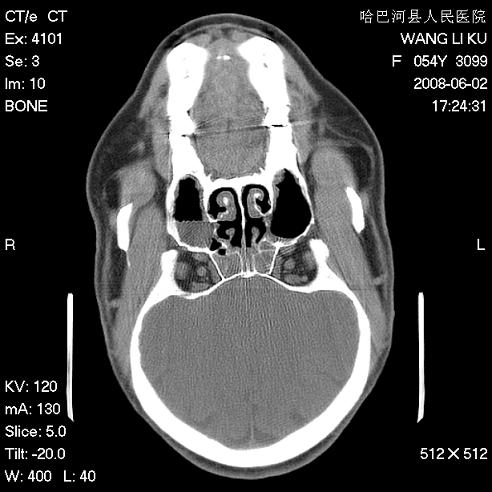

标题: CT13803:反复性鼻塞、流涕一年余 [打印本页]

标题: CT13803:反复性鼻塞、流涕一年余

副鼻窦炎,右上额窦积脓。左眼肌锥内见致密影,视神經受压

1.全组副鼻窦炎2.双侧上颌窦积液

1)全副鼻窦炎(左侧上颌窦黏膜下囊肿或息肉)。2)左眼眶肌锥内不规则小结节状软组织密度影;考虑为小血管瘤可能。建议行ct增强扫描检查。

全组副鼻窦炎,左侧肌锥内不规则形软组织肿块影,与眼外肌密度相当,左侧视神经受压,肿块与视神经及眼外肌分界清晰,眼外肌无增粗,眶壁无破坏,球后脂肪间隙不模糊,考虑良性改变,小血管瘤或神经源性肿瘤可能,建议增强扫描。

谢谢,增强扫描做了,眶内病灶与海绵窦同步明显强化,血管瘤